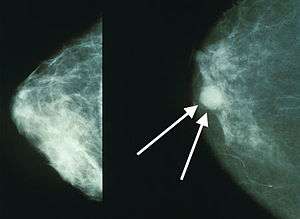

Mammograms showing a normal breast (left) and a breast with cancer (right, white arrows). | |